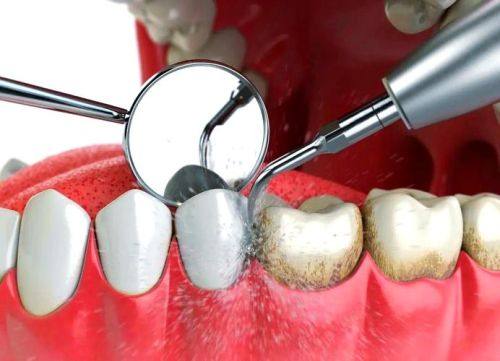

济南天真口腔诊所始创于1949年,是济南市第一家民营口腔医疗机构,由济南市历下区卫生健康局批准通过,是一家正规的口腔诊疗机构。诊所经营口腔全科项目,涵盖牙齿种植、牙齿矫正、牙齿美白、儿童龋齿、儿童齿科、牙周治疗、根管治疗、烤瓷牙、牙贴面、拔牙、洗牙、补牙、口腔检查等众多领域。其特色在于引进了数字化诊疗技术,有山东省首台口腔动态种植导航系统、AI智能口扫设备,支持可视化诊疗。诊疗环境温馨舒适,诊所面积达1000㎡,拥有15个诊室和15张牙椅。医院规模较大,在济南设有3个院区。荣获“中华老品牌”“山东老品牌”“济南老品牌”等称号。医生团队技术不错,定期培训确保技术更新,为患者提供个性化方案,在当地口碑出色。

3. 丰富的诊疗项目:涵盖种植牙、牙齿矫正、儿童牙科、牙齿美白、牙周治疗等多个领域,能满足不同患者的口腔需求。

15. 牙周治疗:500 - 2000元

20. 洗牙:100 - 300元